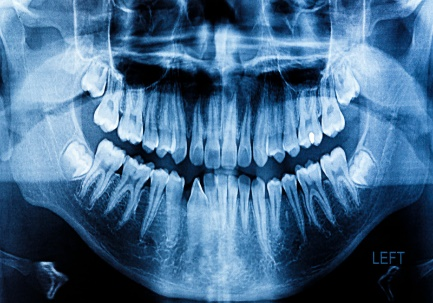

2D Dental Panoramic Tomography

The Dental Panoramic Tomogram (OPG) is a must have for every dental patient because it provides an overview of the entire jaw and all the teeth and surrounding structures on one film.

What Is a Panoramic X-Ray?

A panoramic x-ray is a two-dimensional x-ray that captures a picture of a patient’s entire mouth in just one image. The x-ray includes a view of all of the teeth, multiple bones of the head and neck, and other critical anatomical structures.

Unlike bitewing dental x-rays which show a close up of view of your teeth, this x-ray gives a global view of a patient’s head and neck. This view allows for diagnosing more than just regular dental concerns, like cavities or gum disease. Rather, this view enables the radiologist to see other important issues that may be occurring in the surrounding tissue and jaw bones like oral cancer or other abnormalities, things that would not be visible in an ordinary dental radiograph.